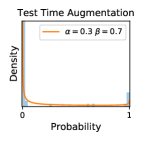

To model how different classifiers will respond to a given input , we assume that the prediction from classifier is sampled from a beta distribution that is characterized by two parameters by and . We further assume that is fixed to the same constant value for all ’s. Under this assumption, each input can be described by ( can be calculated since is fixed), easing further analysis. The Severity Level (SL) of the case represented by image can be characterized by the parameter . The larger the value of , the more severe the case of is. When and are close, the case is ambiguous as the distribution shifts towards being symmetric (i.e. signifying much disagreement among classifiers) rather than being one-sided (i.e. consensus among classifiers that is negative or positive). We provide a set of examples in Figure 2 and also Figure S.8 in the supplementary materials showing how the beta distribution can be used to capture diverse predictions given by an ensemble learner.

In contrast, the MC-dropout method showed the worst overall performance among the three, as it can be seen from the high ratios of SL0 examples among the uncertain negatives in Figure 4. The histograms in Figure 2 provides another perspective to look into the phenomenon, where a decent proportion of MC-dropout model’s predictions on SL0 inputs entailed low confidence (far from 0 or 1), which from another angle explained why MC-dropout was less specific in terms of lower FNP; many no-DR inputs (i.e. SL0) were erroneously assigned high uncertainty by MC-dropout models.

It is still an open question why the evaluated MC-dropout networks signaled relatively high uncertainty on SL0 & SL3 & SL4 data that are less likely to be ambiguous. We conjecture that much of the “uncertainty” indicated by disagreement among test-time dropout samples actually reflects the stochastic nature of dropout networks rather than the real decision uncertainty associated with the data. It is worth noting that the MC-dropout model we evaluated was not weak per se; they all achieved above Area Under Curve (AUC) scores on test sets. The weakness of individual test-time samples (which explains their low-confidence predictions on SL0 & SL3 & SL4) might have been hidden when they are aggregated into an ensemble—a well-known advantage of ensemble learning. Our results suggested that the uncertainty information given by implicit ensemble methods such as MC-dropout and TTA might not be as reliable as that from explicit ensemble approaches (e.g., stacking ensembles). Similar findings on MC-dropout can be found in some previous papers [1].